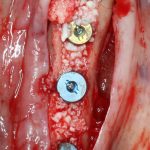

Кстати, обрати внимание на ширину альвеолярного гребня (левая картинка). Она чуть меньше 3 мм. Это объясняет, почему я засомневался в возможности установки имплантатов одновременно с остеопластикой. Понятно и без КЛКТ.

Возвращаемся к основной операционной области. Еще раз посмотрим на альвеолярный гребень, поофигеваем от его ширины и моих грандиозных планов: